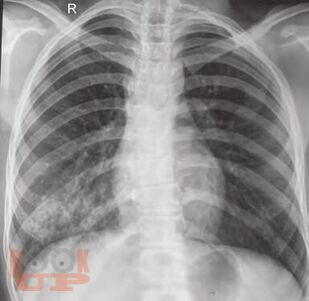

Covering various aspects of respiratory diseases in children. Multiauthored book, extensively updated by experts. Provides the key details of anatomy and applied physiology. The section on investigations has been expanded to include advanced lab investigations, pulmonary functions, and molecular tests. Common as well as rare infections, include COVID-19 infection have been covered in the section on respiratory infections. The section on noninfectious diseases covers various aspects of asthma, sarcoidosis, eosinophilic lung diseases, hydrocarbon aspirations, central hypoventilation, pulmonary hemorrhage, etc. The emerging illnesses such as primary ciliary dyskinesia, cystic fibrosis, interstitial lung diseases, etc. described in detail. These will be useful for India and other resource-limited countries. The section on acute pulmonary care including acute lung injury, mechanical ventilation monitoring and airway clearance technique that may be of immense help to practicing pediatricians who provide care for pediatric respiratory illnesses. Surgical issues that are essential for pediatricians including foreign body aspirations, intrathoracic tumors and malformations have been included. There are chapters on genetics of lung diseases, sudden infant deaths syndrome, drug and environmental diseases of lung.